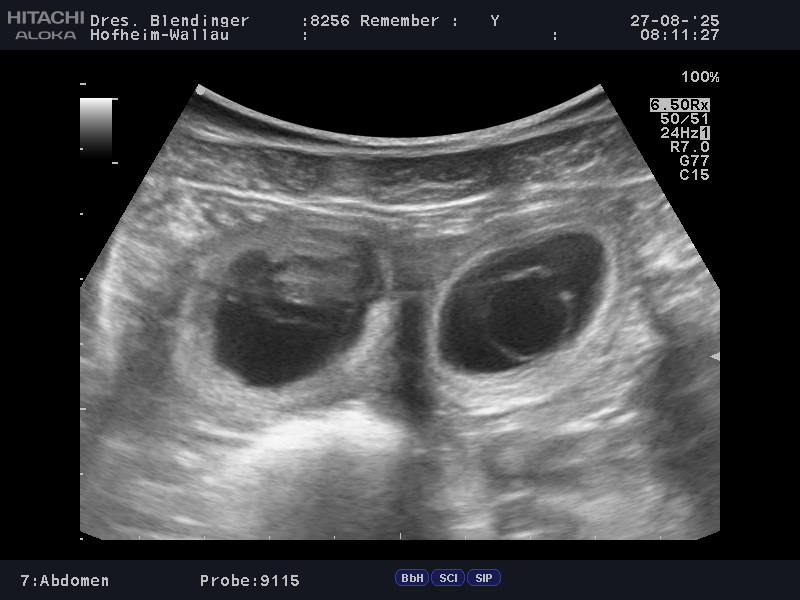

Nach dem positiven Ultraschallbefund heute ist es amtlich… Unser Mädel ist trächtig !!! Remember hat damit gezeigt, dass sie sich doch in die erfolgreichen fruchtbaren Ahnen (mütterlich) einreihen kann. Die Tierärztin konnte 6-8 Fruchtblasen erkennen.